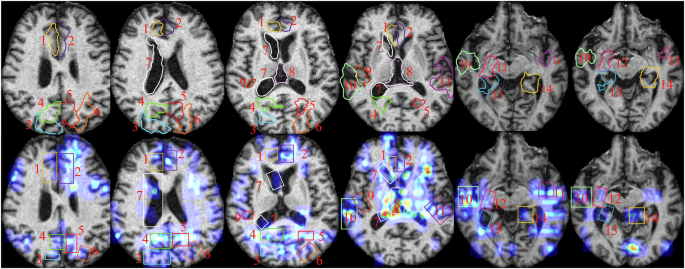

Clinician validation and Brain Atlas validation

To quantitatively evaluate the interpretability and annotation accuracy of CAGM, we utilized BrainSuite software to perform brain segmentation on MRI images. Subsequently, the lesion annotations generated by CAGM were compared with those of the segmented images. The Brain Atlas validation comparison chart is shown in Fig. 3. Our evaluation indicates that CAGM annotations are perfectly distributed in brain regions vulnerable to AD, such as the hippocampus and amygdala, aligning seamlessly with anatomical structures. Furthermore, the overlap rate of CAGM annotation regions with standard brain atlases reaches 83.21%. Compared to manual annotations by expert clinicians from 10 patients (Fig. 4), the overall Dice Similarity Coefficient (ODS) achieves 83.6%, calculated using the following formula:

Brain Atlas validation comparison chart.

Presents a comparative example of manual annotations by clinicians and automatic annotations generated by CAGM, highlighting key brain anatomical structures (regions of atrophy or abnormal enlargement) as follows: 1 is R. cingulate gyrus, 2 is L. cingulate gyrus, 3 is R. superior parietal gyrus, 4 is R. pre-cuneus, 5 is L. pre-cuneus, 6 is L. cingulate gyrus, 7 is R. lateral ventricle, 8 is third ventricle, 9 is R. transverse temporal, 10 is R. superior temporal gyrus, 11 is L. superior temporal gyrus, 12 is Bilateral Hippocampus, 13 is R. parahippocampal gyrus, and 14 is L. parahippocampal gyrus. This comparison enables a visual evaluation of the consistency and potential discrepancies in CAGM annotations across cortical and subcortical structures, serving as a reference for subsequent quantitative analysis.